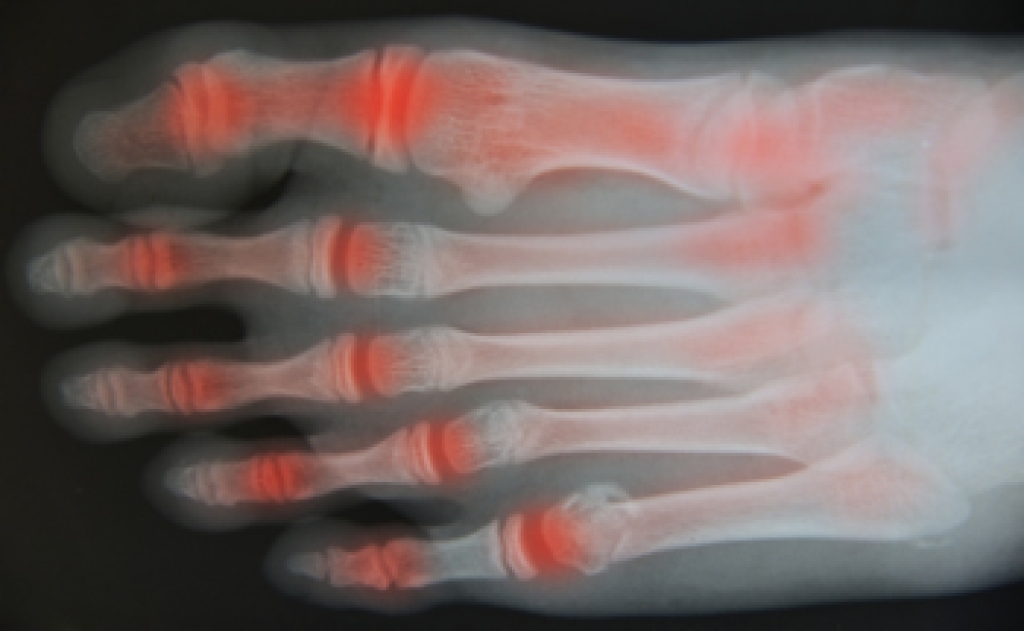

Arthritic Foot Care

Arthritis is a term that is commonly used to describe joint pain. The condition itself can occur to anyone of any age, race, or gender, and there are over 100 types of it. Nevertheless, arthritis is more commonly found in women compared to men, and it is also more prevalent in those who are overweight. The causes of arthritis vary depending on which type of arthritis you have. Osteoarthritis for example, is often caused by injury, while rheumatoid arthritis is caused by a misdirected immune system.

- Swelling

- Pain

- Stiffness

- Decreased Range of Motion

Arthritic symptoms range in severity, and they may come and go. Some symptoms stay the same for several years but could potentially get worse with time. Severe cases of arthritis can prevent its sufferers from performing daily activities and make walking difficult.